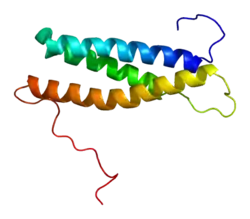

Spartin is a protein that in humans is encoded by the SPG20 gene.[3][4][5]

This gene encodes a protein that contains a MIT (Microtubule Interacting and Trafficking molecule) domain. This protein may be involved in endosomal trafficking, microtubule dynamics, or both functions. Spartin loss has been associated to mitochondrial dysfunction, impaired complex I activity and altered pyruvate metabolism.[6] Frameshift mutations associated with this gene cause autosomal recessive spastic paraplegia 20 (Troyer syndrome).[5] Troyer syndrome (SPG20) is a complicated type of hereditary spastic paraplegias (HSPs).[7] HSP is a category of neurological disorder characterized by spasticity and muscle weakness in the lower limbs.[7]